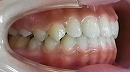

治療前 治療後

今回の症例は小学3年生です。

治療の方向性として、受け口に対するだけでなく、

トータルに咬み合わせのバランスを改善していく事により

特に鼻の機能の向上を狙っています。

治療期間は1年6カ月です。

独自の方法及びムー・i-3等によって改善しています。